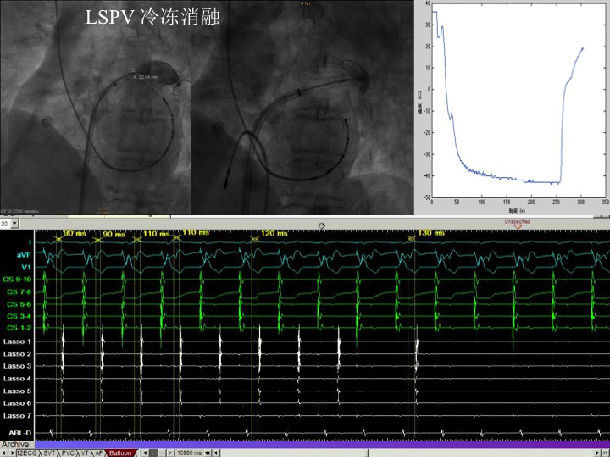

冷冻球囊导管消融举例: